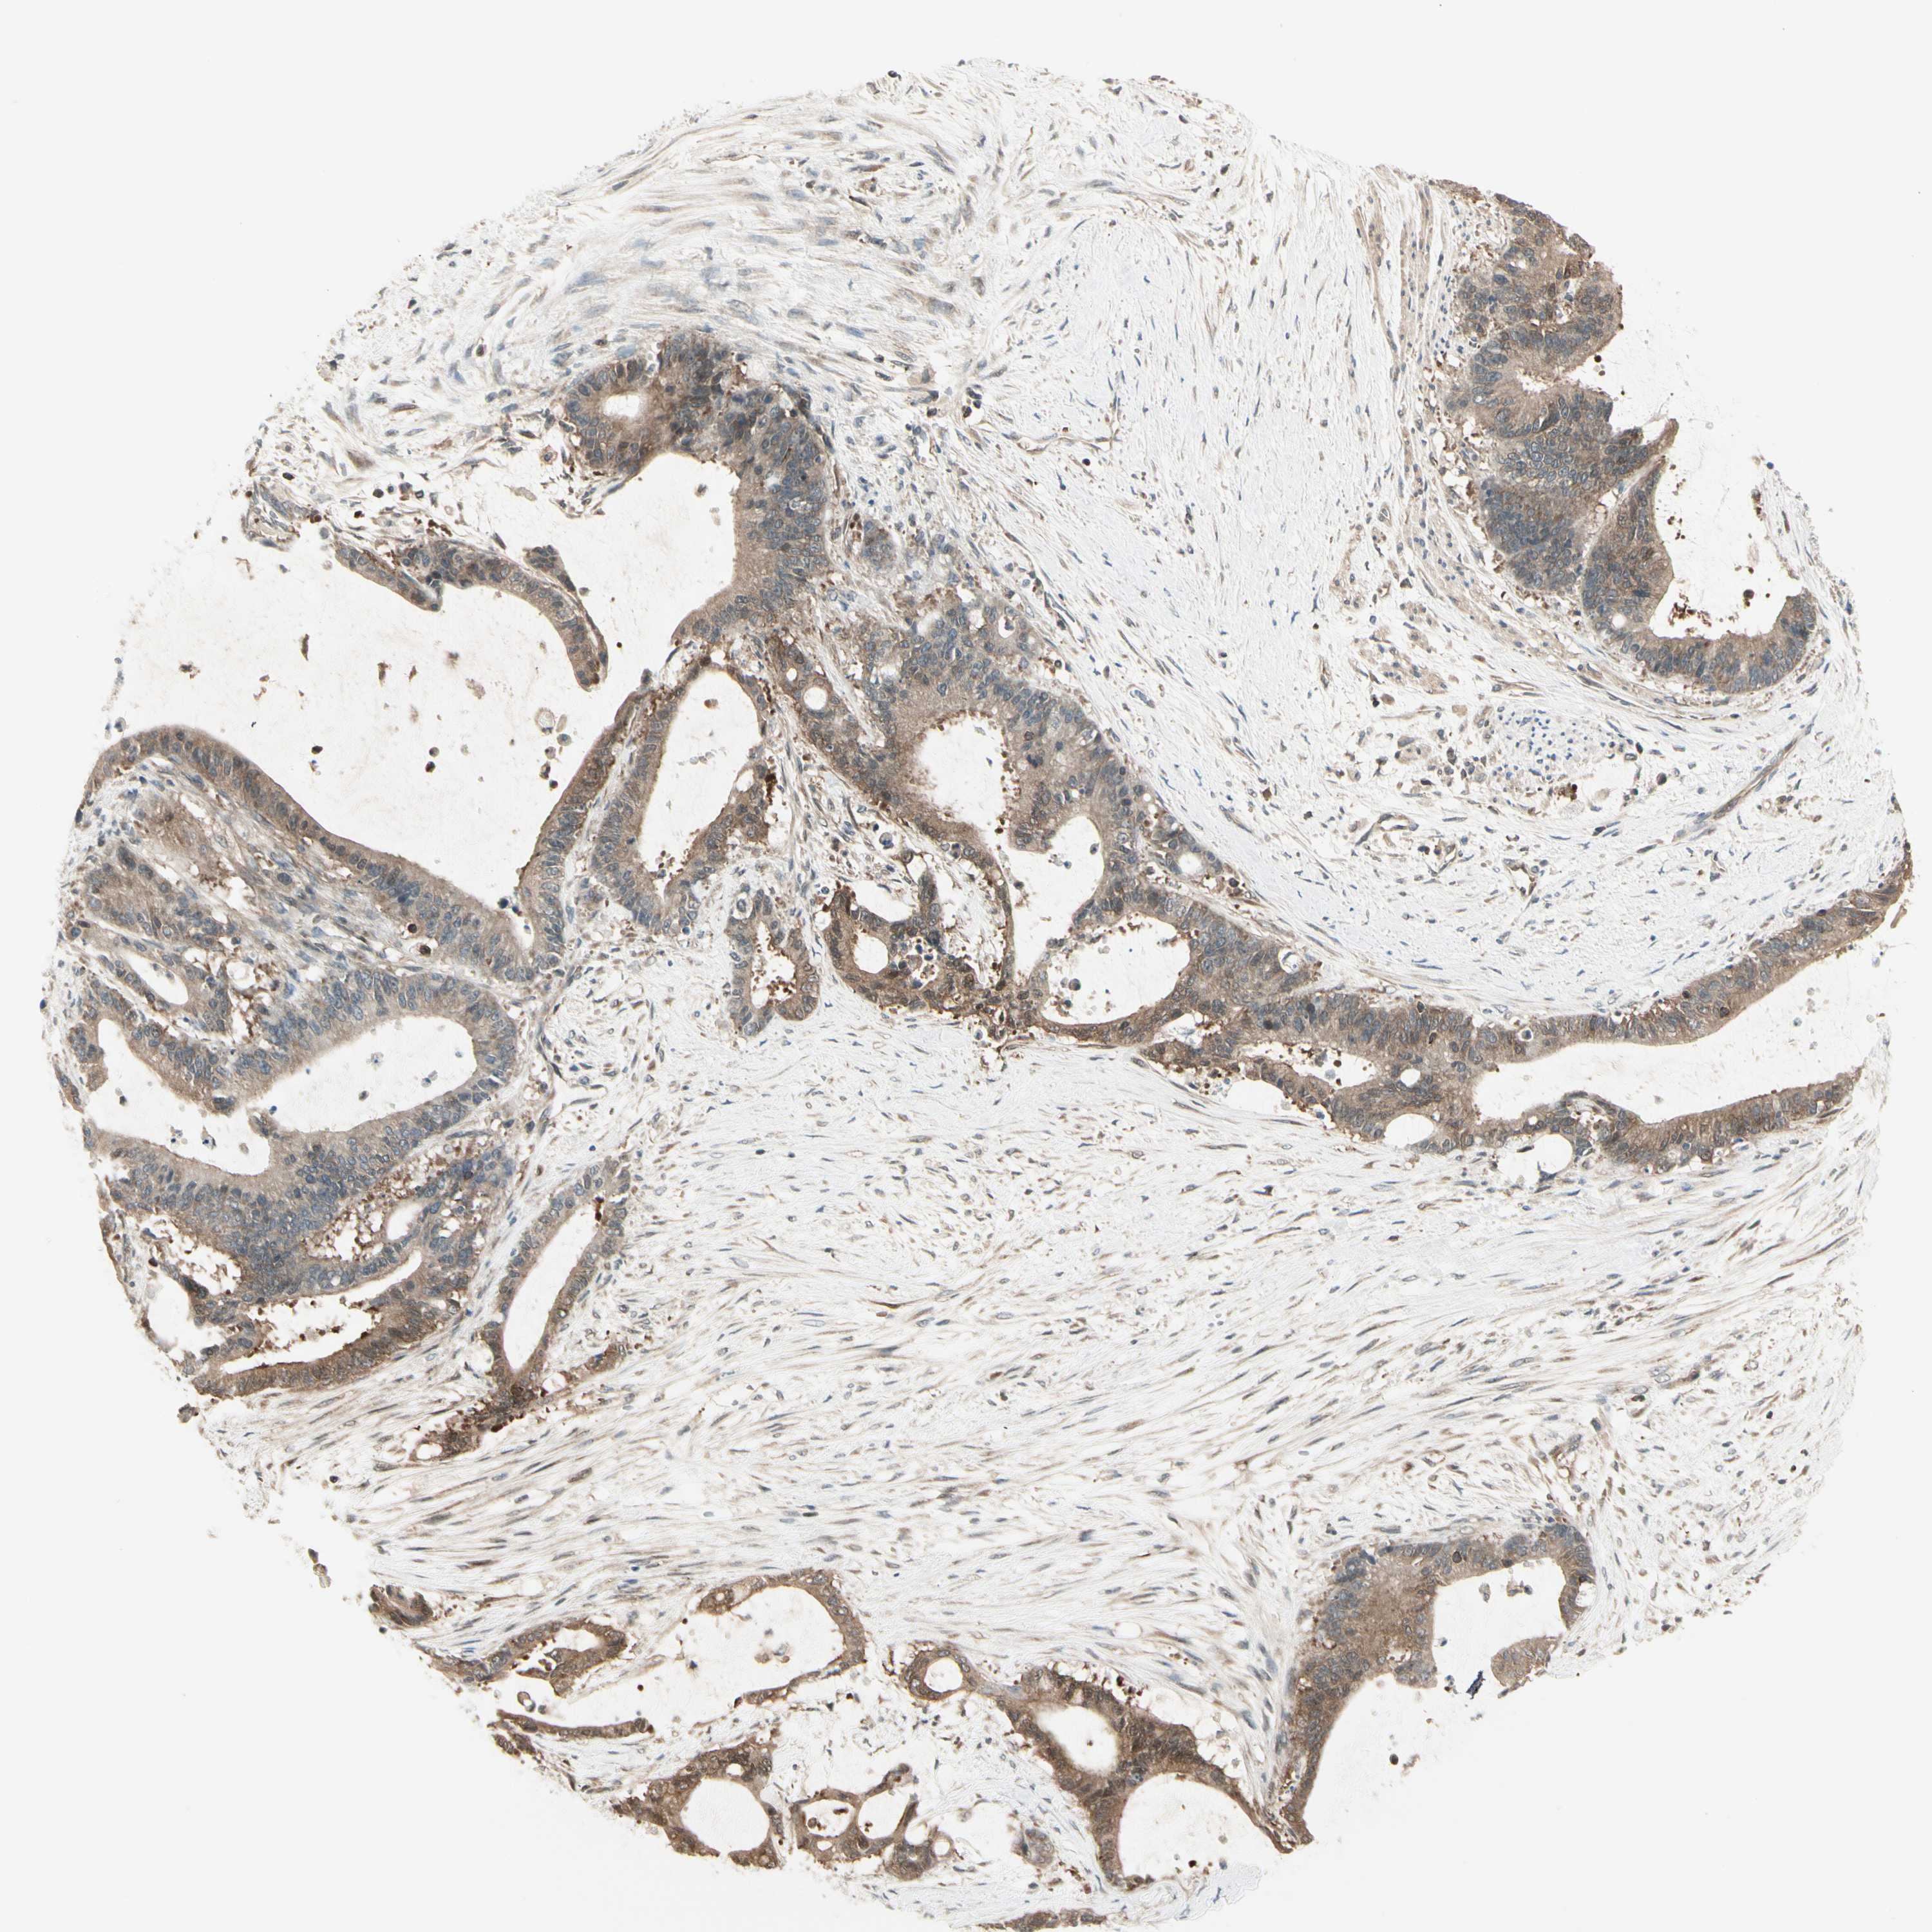

LIVER CANCER - Protein expressioni

A mouse-over function shows sample information and annotation data. Click on an image to view it in a full screen mode. Samples can be filtered based on level of antibody staining by selecting one or several of the following categories: high, medium, low and not detected. The assay and annotation is described here.

Note that samples used for immunohistochemistry by the Human Protein Atlas do not correspond to samples in the TCGA dataset.

Antibody stainingi

Antibody staining in the annotated cell types in the current human tissue is reported as not detected, low, medium, or high, based on conventional immunohistochemistry profiling in selected tissues. This score is based on the combination of the staining intensity and fraction of stained cells.

Each image is clickable and will lead to virtual microscopy that enables deeper exploration of all samples and also displays staining intensity scores, fraction scores and subcellular localization as well as patient and tissue information for each sample.

Antibody HPA008237

Antibody CAB017181

Staining

High

Medium

Low

Not detected

Intensity

Strong

Moderate

Weak

Negative

Quantity

>75%

75%-25%

<25%

None

Location

Nuclear

Cytoplasmic/membranous

Cytoplasmic/membranous,nuclear

Cholangiocarcinoma

Carcinoma, Hepatocellular, NOS